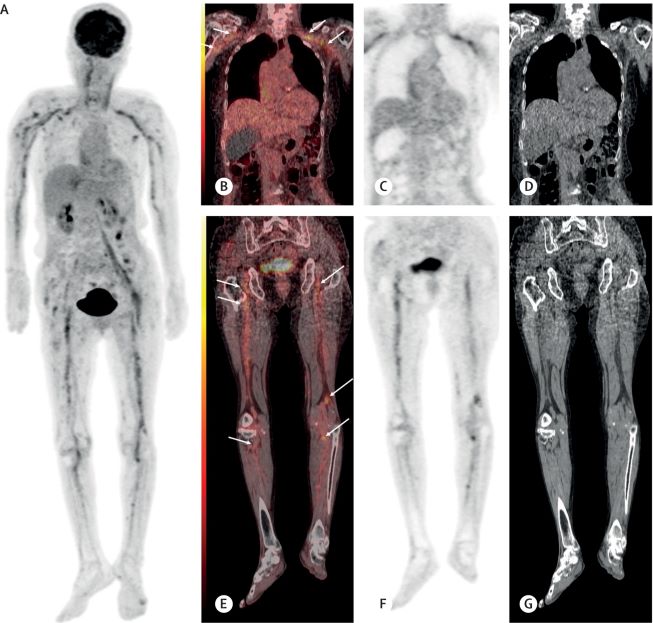

¡ã¹Ì¸¸¼º °Å´ëB¼¼Æ÷¸²ÇÁÁ¾ ȯÀÚ¿¡¼­ ¸»ÃʽŰæÀ» µû¶ó ¿°Áõ ¹ÝÀÀÀÌ °üÂûµÈ À̹ÌÁö [Ãâó=±¹¸³¾Ï¼¾ÅÍ]

ÇÑÆí, ¿¬±¸ÁøÀº ¹Ì¸¸¼º °Å´ëB¼¼Æ÷¸²ÇÁÁ¾À» ¾Î¾Ò°í º¹ÇÕ ¸é¿ªÇ×¾ÏÈ­Çпä¹ýÀ» ¹Þ¾Ò´ø ȯÀڵ鿡°Ô ±Þ¼º¸¶ºñ°¡ ¹ß»ýÇØ ¸²ÇÁÁ¾ÀÇ Àç¹ß °¡´É¼ºÀ» ¹èÁ¦Çϱâ À§ÇØ Æ÷µµ´ç À¯»çü ¾çÀüÀÚ ¹æÃâ ´ÜÃþÃÔ¿µ°Ë»ç¸¦ ÁøÇàÇß´Ù. ±× °á°ú, ±Þ¼º¸¶ºñ°¡ ³ªÅ¸³­ ºÎÀ§¿Í °ü·ÃµÈ ¸»ÃʽŰæÀÇ ¿°Áõ¹ÝÀÀÀ» °üÂûÇÒ ¼ö ÀÖ¾ú´Ù. ÀÌ´Â ±æ¶û-¹Ù·¹ ÁõÈıº ¼Ò°ßÀ» º¸ÀΠȯÀÚÀÇ ¼¼°è ÃÖÃÊ ¾çÀüÀÚ ¹æÃâ ´ÜÃþÃÔ¿µ º¸°í¶ó´Â Àǹ̰¡ ÀÖ´Ù.